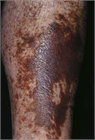

1. 下肢静脈瘤の患者に対しては、CEAP分類を用いて臨床的重症度や病態を評価することを推奨する(推奨度1)